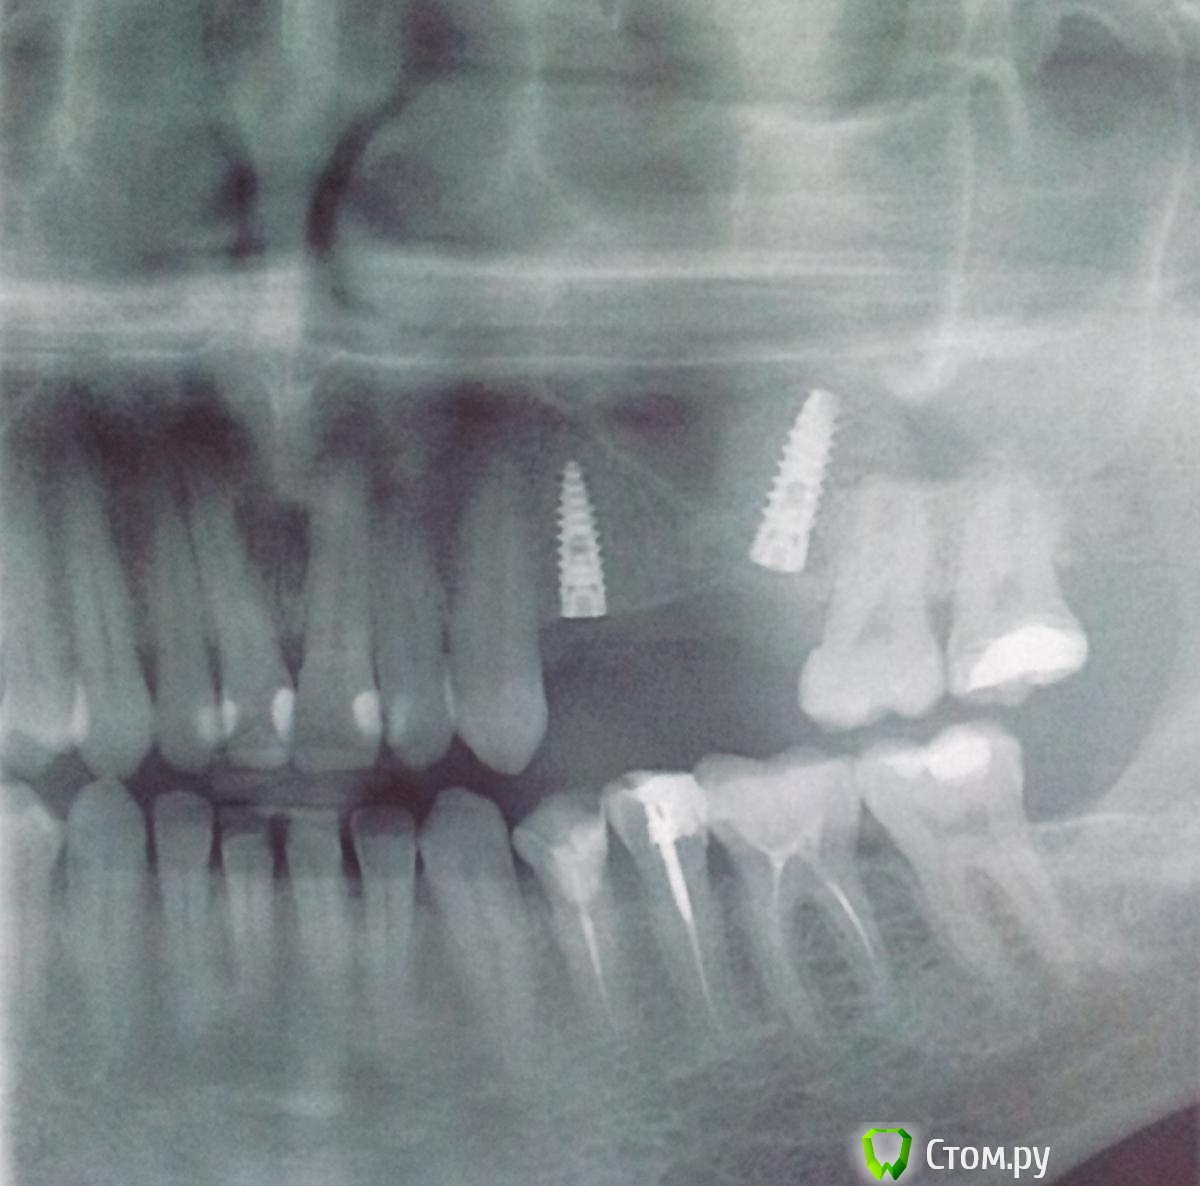

Пациент Ю Опубликовано 24 марта, 2014 Автор Поделиться Опубликовано 24 марта, 2014 Вот и удалили имплант. теперь три месяца ждём. А пока снимки что есть на руках. Виноватых не найти. Все по своему правы. Ссылка на комментарий

SDC Опубликовано 7 сентября, 2014 Поделиться Опубликовано 7 сентября, 2014 Вот и удалили имплант. теперь три месяца ждём. А пока снимки что есть на руках. Виноватых не найти. Все по своему правы.Ю, Вы хороший человек. Хочется пожелать Вам удачи и хорошего лечения.Пока есть время, займитесь антагонистами - велик риск их перелома, когда появятся коронки на имплантатах на в.ч. Ссылка на комментарий